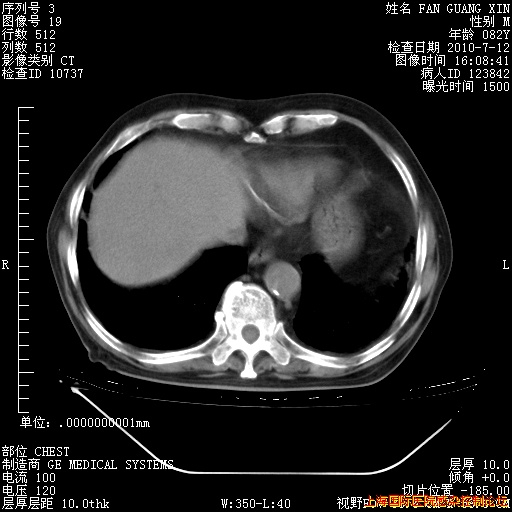

今天复查CT

今天CT

整整相隔30天的肺部CT好像有所好转啊。甲强龙减量第3天,需要观察体温。